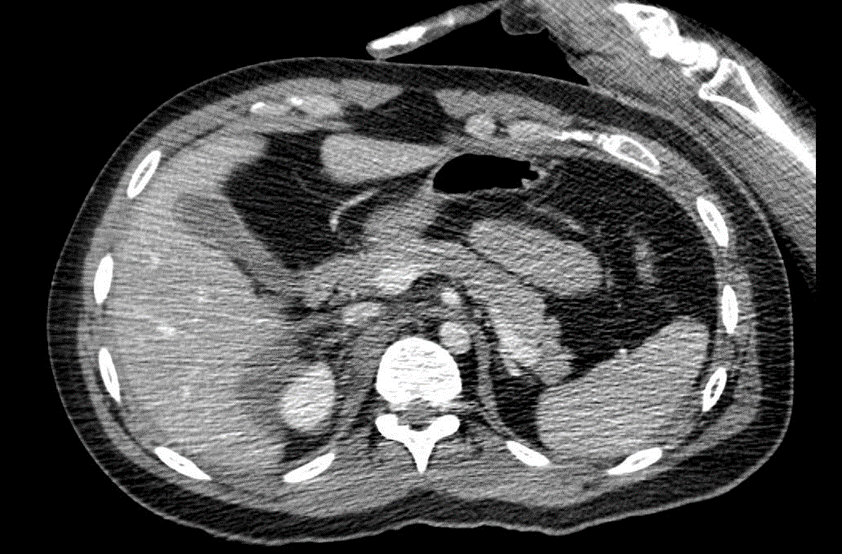

TC abdome e pelve com contraste endovenoso (EV) (02/04/2025): Derrame pleural bilateral – Hemoperitônio disperso na cavidade. Aumento e borramento da adrenal direita, inferindo contusão / laceração. Fígado, pâncreas e adrenal esquerda com situação, dimensões, contornos e coeficientes de atenuação normais. Baço homogêneo. Linha tênue no contorno superior do baço de difícil caracterização devido a artefatos. Ausência de sinais de dilatação das vias biliares intra ou extra-hepáticas. Vesícula biliar normodistendida, paredes finas e conteúdo homogêneo. Rins com topografia, morfologia, dimensões, eixo, contornos e espessura do parênquima normais, não se observando sinais de dilatação dos sistemas coletores. Boa concentração e eliminação do meio de contraste, bilateralmente. Aorta e veia cava inferior com calibre e contornos normais. Ausência de linfonodomegalias retroperitoneais e pélvica. Bexiga repleta, apresentando contornos regulares e conteúdo homogêneo. Próstata com contornos regulares e densidade tomográfica preservada. Trato gastrointestinal de aspecto habitual. Hérnia umbilical, com conteúdo lipomatoso. Fratura cominutiva do colo femoral direito, com desvio.

Figura 5: Tomografia Computadorizada de abdome.

Figura 6: Tomografia Computadorizada de abdome.

TC abdome e pelve com contraste EV (03/04/25): Derrame pleural bilateral, determinando atelectasia passiva. Hematoma adrenal direita medindo 3 cm. Moderado hemoperitônio. Pequeno borramento da gordura perirrenal direita. Fratura em colo femoral direito com desvio. Sem demais alterações agudas do trauma.

Figura 7: Tomografia Computadorizada de abdome.